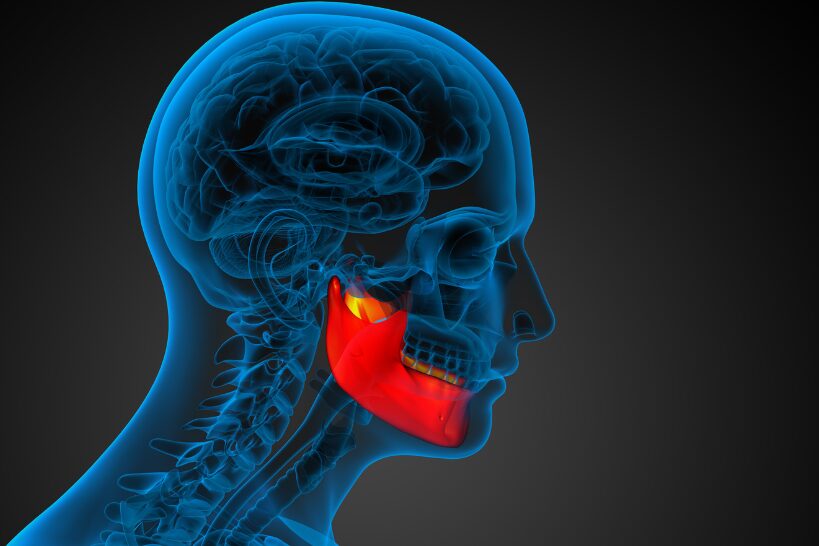

The Causes of Jaw Dysfunction

TMD often results from a combination of factors stressing the jaw joint. A primary cause is teeth clenching or grinding (bruxism) during sleep, which inflames the TMJ and fatigues muscles. Stress also contributes by causing subconscious jaw tightening. Misaligned teeth or jaws (malocclusion) force muscles to overcompensate. Other causes include arthritis or direct jaw injury, which can damage the joint’s cartilage or disc.